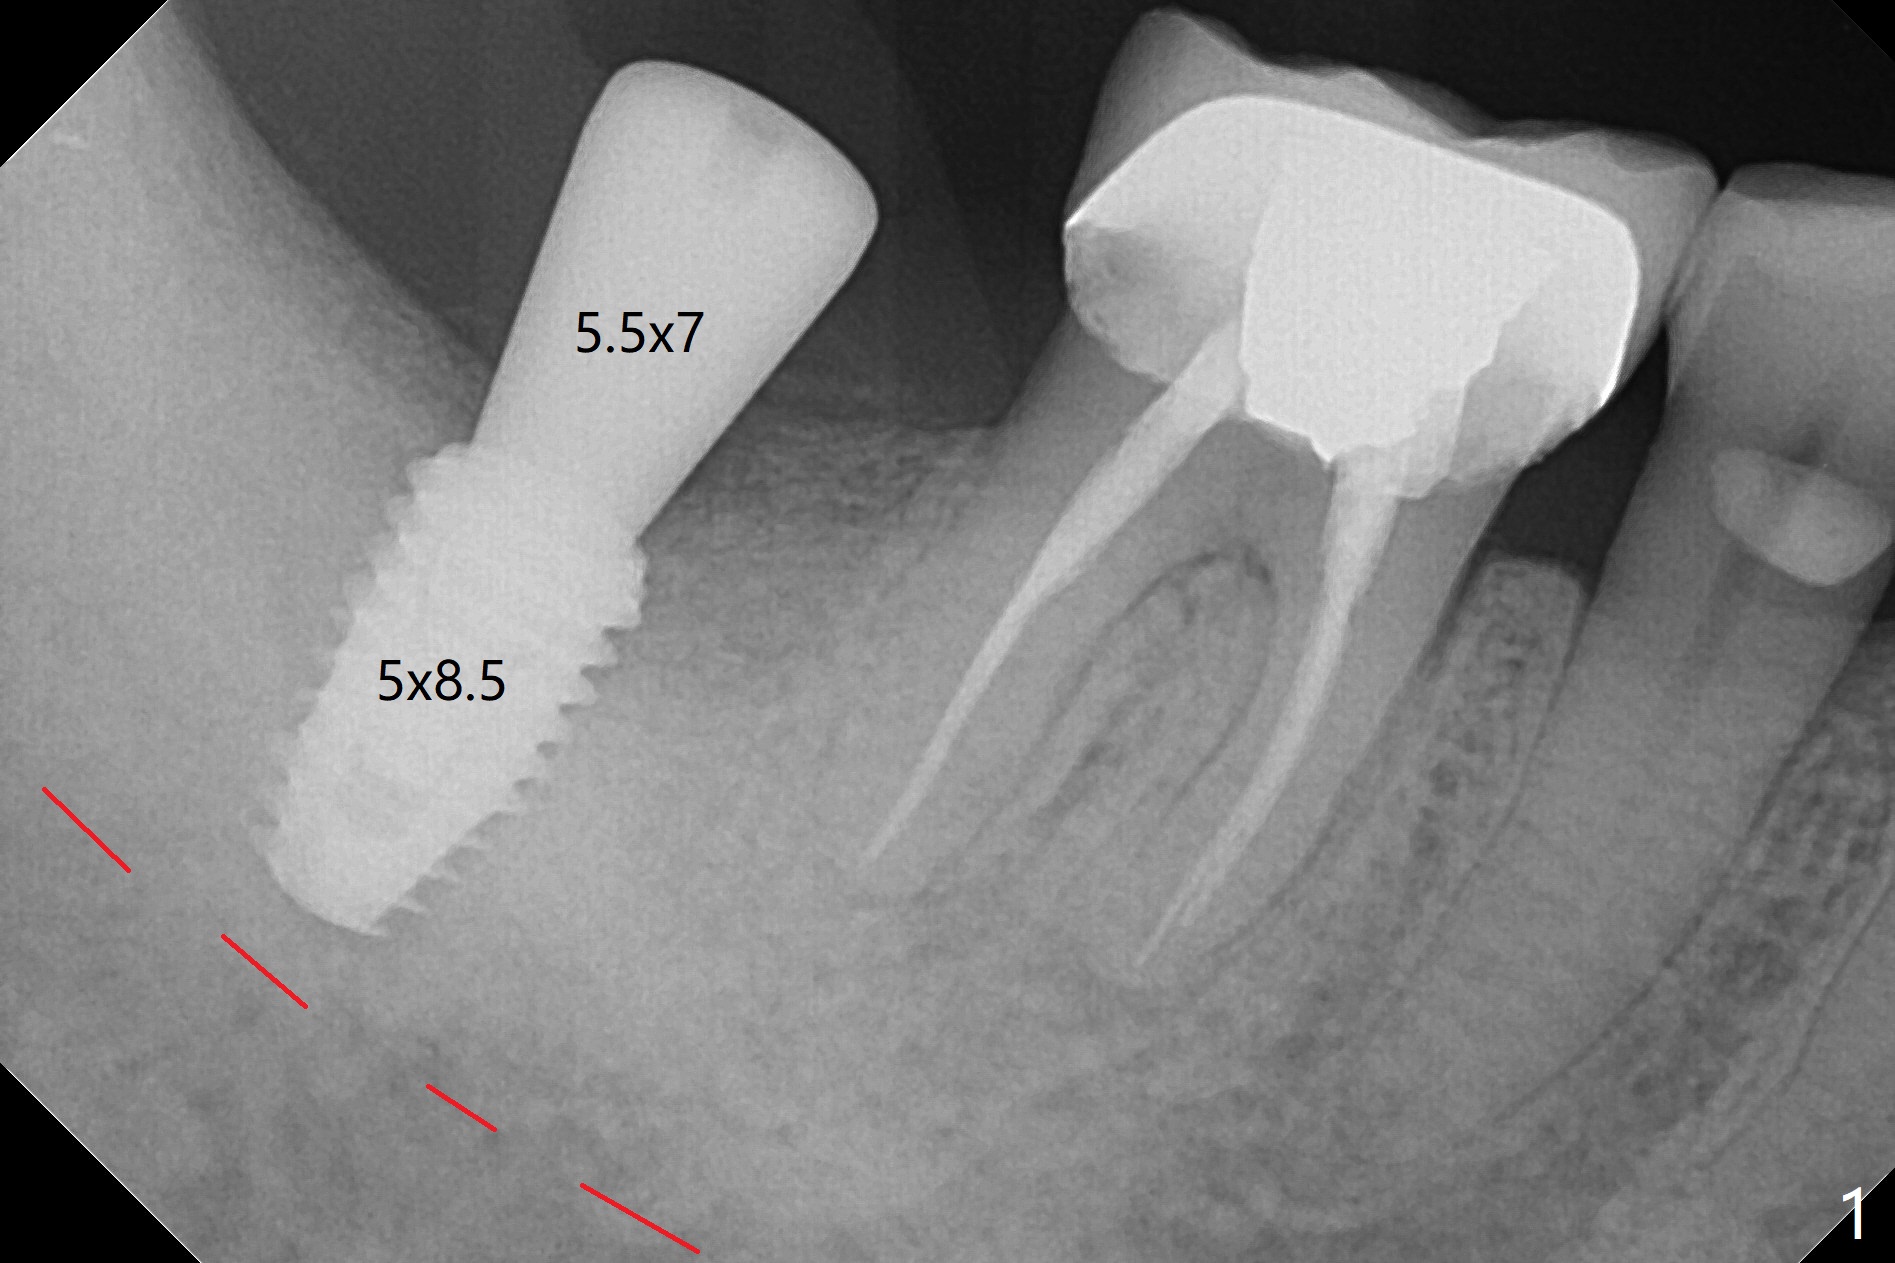

Jennifer: Today's case went on well thanks to our repeated conversation.   I have one question: why I had resistance using the last drill 4.5x10 mm.  I had to remove the drill and remove the bone from the drill and reentered the osteotomy.  My heart sank when 4.5 mm cortical tap (according to drill sequence) had no resistance.  Luckily the 5x8.5 mm implant achieved primary stability in the final 1-2 mm.  The O-ring was removed.  The implant was then placed ~ .5 mm deeper (~ 40 Ncm) (Fig.1).  Thanks as usual.

When you look at the bottom part divided by the red line. It is very dense bone. However when I looked at the upper part from the red line even it showed high HU around 1000, but still as it is grafted bone, it may have not had the actual fixing stability at the top. That's why you might have felt that tapping which goes down 3mm at the top for the cortical bone has low resistance.  However, those white dense part at the apex helped to hold the implant firmly to achieve the torque.

So to answer your questions,  why I had resistance using the last drill 4.5x10mm.  I had to remove the drill and remove the bone from the drill and reentered the osteotomy. That part you felt high resistance was the dense bone you got the fixation from. And for those dense part, those bone comes out inside the blade of osteotomy drill and like you did, scrape it out and if necessary, you may redo the drilling. Dr. Heo, the founder of the Neobiotech does that too.  Jennifer